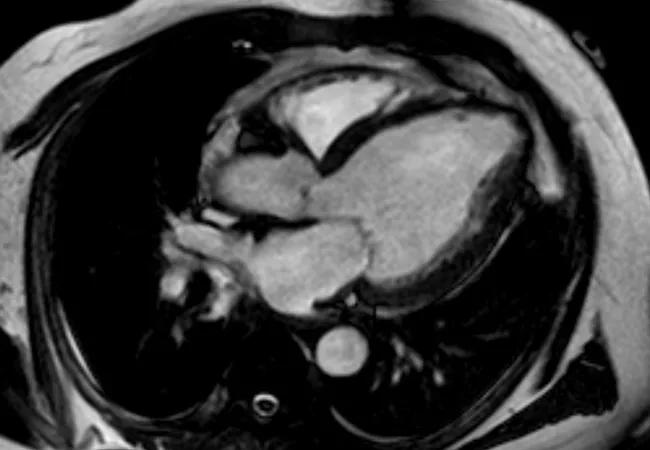

Cleveland Clinic completed the procedure in one ALIVE trial enrollee in late 2020 (Figure) and anticipates enrolling several additional patients this year.

Figure. Axial MRIs taken before (left) and after (right) the Revivent procedure.